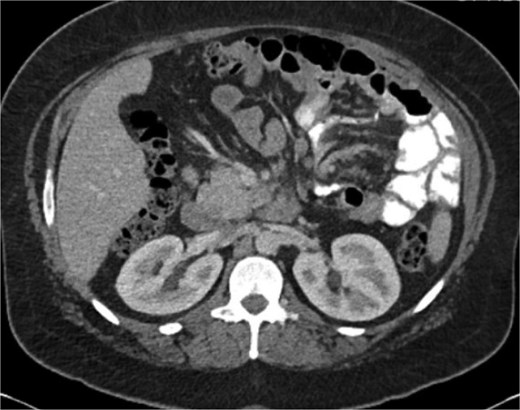

A 38-year-old female (Gravida 5, Para 2) at 30 weeks and 1 day gestation with history of a LRYGB performed to treat gastroparesis in the setting of morbid obesity presented to the Emergency Department with acute-onset severe epigastric pain exacerbated by eating. She reported associated nausea and diarrhea, and denied emesis, heartburn, fever, constipation, or dysuria. She was hemodynamically normal with normal fetal heart tones and laboratory results. She underwent esophagogastroduodenoscopy, which revealed a normal-appearing gastric pouch and jejunal mucosa, without evidence of a marginal ulcer. Abdominopelvic CT imaging demonstrated mesenteric swirling with clustering of small intestines entirely on the left abdomen suspicious for IH (Figs 1 and 2). Fluoroscopic small bowel follow through did not demonstrate evidence of small intestinal obstruction. On hospital Day 9, she remained unable to tolerate oral intake, and after multidisciplinary discussion with providers and the patient, she was scheduled for surgical repair.

Coronal CT demonstrating left upper quadrant mesenteric swirling with cluster of small intestine entirely on the left abdomen.